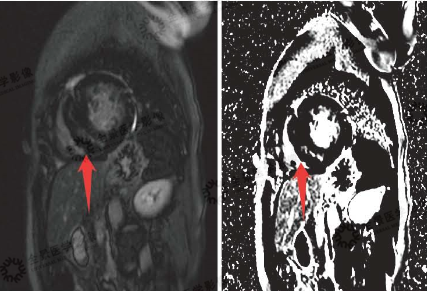

▲灌注序列

红色箭头:缺血区域充盈缺损表现

磁共振显示:该患者冠心病,心肌梗死,梗死心肌占左室总体60%,前降支供血区透壁性心肌梗死;右冠状动脉、旋支供血区基底部及中间段大部分心肌存活,心尖段心肌透壁性梗死。全心增大,心功能不全。

▲延迟强化序列

基底段-中央段间隔量、心尖段前型,间隔型、下型、侧整心肌中层可见条片状延迟强化(红色箭头)

心脏磁共振显示:非对称性肥厚型心肌病,间隔壁多发心肌纤维化,左心房大;主动脉瓣重度狭窄;二尖瓣反流。